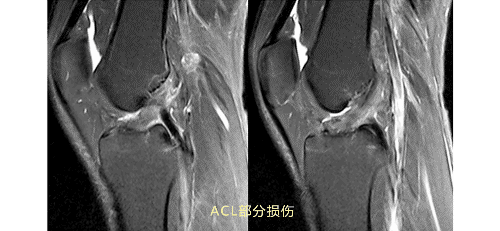

ACL损伤的MRI分级——

Grade1:韧带内损伤,无长度改变。

Grade2:韧带内损伤并长度延长。

Grade3:完全性韧带撕裂。

Grade1、2级为韧带的部分损伤,Grade3级为韧带的完全断裂。